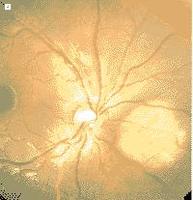

(1)急性期:初期主要眼底特徵是在後極部視網膜血管下有多發的、邊界不清、大片狀黃白色、不規則病灶,呈地圖樣形態,以視盤為中心向黃斑部及赤道部擴展。病灶可反覆再發,在急性病灶中夾雜視網膜脈絡膜萎縮灶 病灶周圍有黃白色進行邊緣,並向病灶周圍正常視網膜血管下深層組織侵犯,呈匐行狀改變。病灶淺面的視網膜水腫 視網膜血管充盈擴張。視盤水腫,有人報導有炎性細胞在玻璃體內,但也有認為無任何炎症現象者 黃斑部及其他部位的視網膜下可有出血,並伴有後極部漿液性視網膜或色素上皮脫離及黃白色滲出物(圖1)。病變消退或痊癒後6~8周又可再次復發,病變在陳舊病灶基礎上向周圍延伸,病灶的中央有視網膜脈絡膜萎縮斑,邊緣病變呈匐行性,向正常視網膜血管下深層組織侵犯。

1.眼底螢光血管造影 早期病變活動時,動脈期病變區呈現弱螢光。這是由於組織水腫遮蔽,或脈絡膜毛細血管遲緩充盈或不充盈,但弱螢光的邊緣部分顯示強螢光。造影晚期病變區組織著色,出現強螢光。視盤毛細血管擴張並有螢光滲漏,視網膜靜脈充盈。管壁增厚,並有滲漏。在病變瘢痕期造影時,因病灶區脈絡膜毛細血管和RPE消失,視網膜下有瘢痕組織遮擋,出現不規則螢光暗區,但脈絡膜大血管及周圍的脈絡膜毛細血管顯影正常,這是由於從邊緣附近的正常的脈絡膜毛細血管向瘢痕區的彌散,造影晚期,病變區組織著色,呈現均勻一致的強螢光(圖2) 。